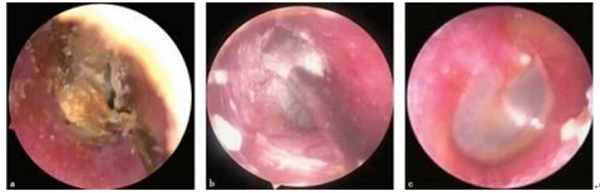

宜春学院第一附属医院 万载县人民医院耳鼻咽喉科黄德虎医生分享了一个病例:一名女病人,因为耳朵痒了1年、一直不缓解,到了“奇痒难忍、寝食难安”的程度,耳道还不断流出有臭味的分泌物,因此到了耳鼻喉科就诊。经耳内镜检查,这名病人耳朵竟得了脚气,医学上称真菌性外耳道炎。黄德虎医生引用病人原话说:“采耳店有一种鹅毛棒,巨爽无比,每次耳朵痒都要去。等到发现自己想戒又戒不掉的时候,就该改道来耳鼻咽喉科了。”

真菌性外耳道炎虽然是条件致病菌所引起,预后良好,但较长的病程、疾病的痛苦以及反复的发作严重影响到患者的生活质量及其心理健康,带来较大的疾病负担,对该病的及时诊治将使患者获得极大的益处。我院耳内镜下使用派瑞松疗法收到良好的治疗效果。

a.用钩针、吸管等显微器械将真菌与外耳道皮肤之间分离;b.采用吸管仔细从外耳道及鼓膜表面分离真菌;c.使用细长棉签外耳道表面均匀涂派瑞松乳膏; 由于耳颞区的解剖特点及血迷路屏障的存在,局部途径用药可使药物直接作用于病变部位,充分发挥最大药效。因此耳部疾病的治疗,耳局部用药已成为常用和有效的治疗手段。传统的耳部局部用药方式主要以滴药、浸泡为主,药物可以直接作用于暴露的外、中耳,但对于某些局限性病灶反而不能针对性地精确用药。耳内镜下的耳部给药则更为细致,例如在内镜监视下使用耳科电凝对局灶性病变进行烧灼,可以避免损伤周围正常组织。对于传统的耳部滴药,在患者伴外耳道耵聍、痂皮及分泌物等堵塞时必然会影响药物到达作用部位。在用药前应用耳内镜充分清理后可以准确地投药至所需部位,在局部形成数十甚至数百倍于全身应用时的药物浓度,迅速达到峰值药物浓度,并长时间维持; 虽然局部形成极高的药物浓度,但用药总量及进入血液循环的药量明显少于全身用药,因而大大减少对全身重要脏器产生的毒性不良反应。